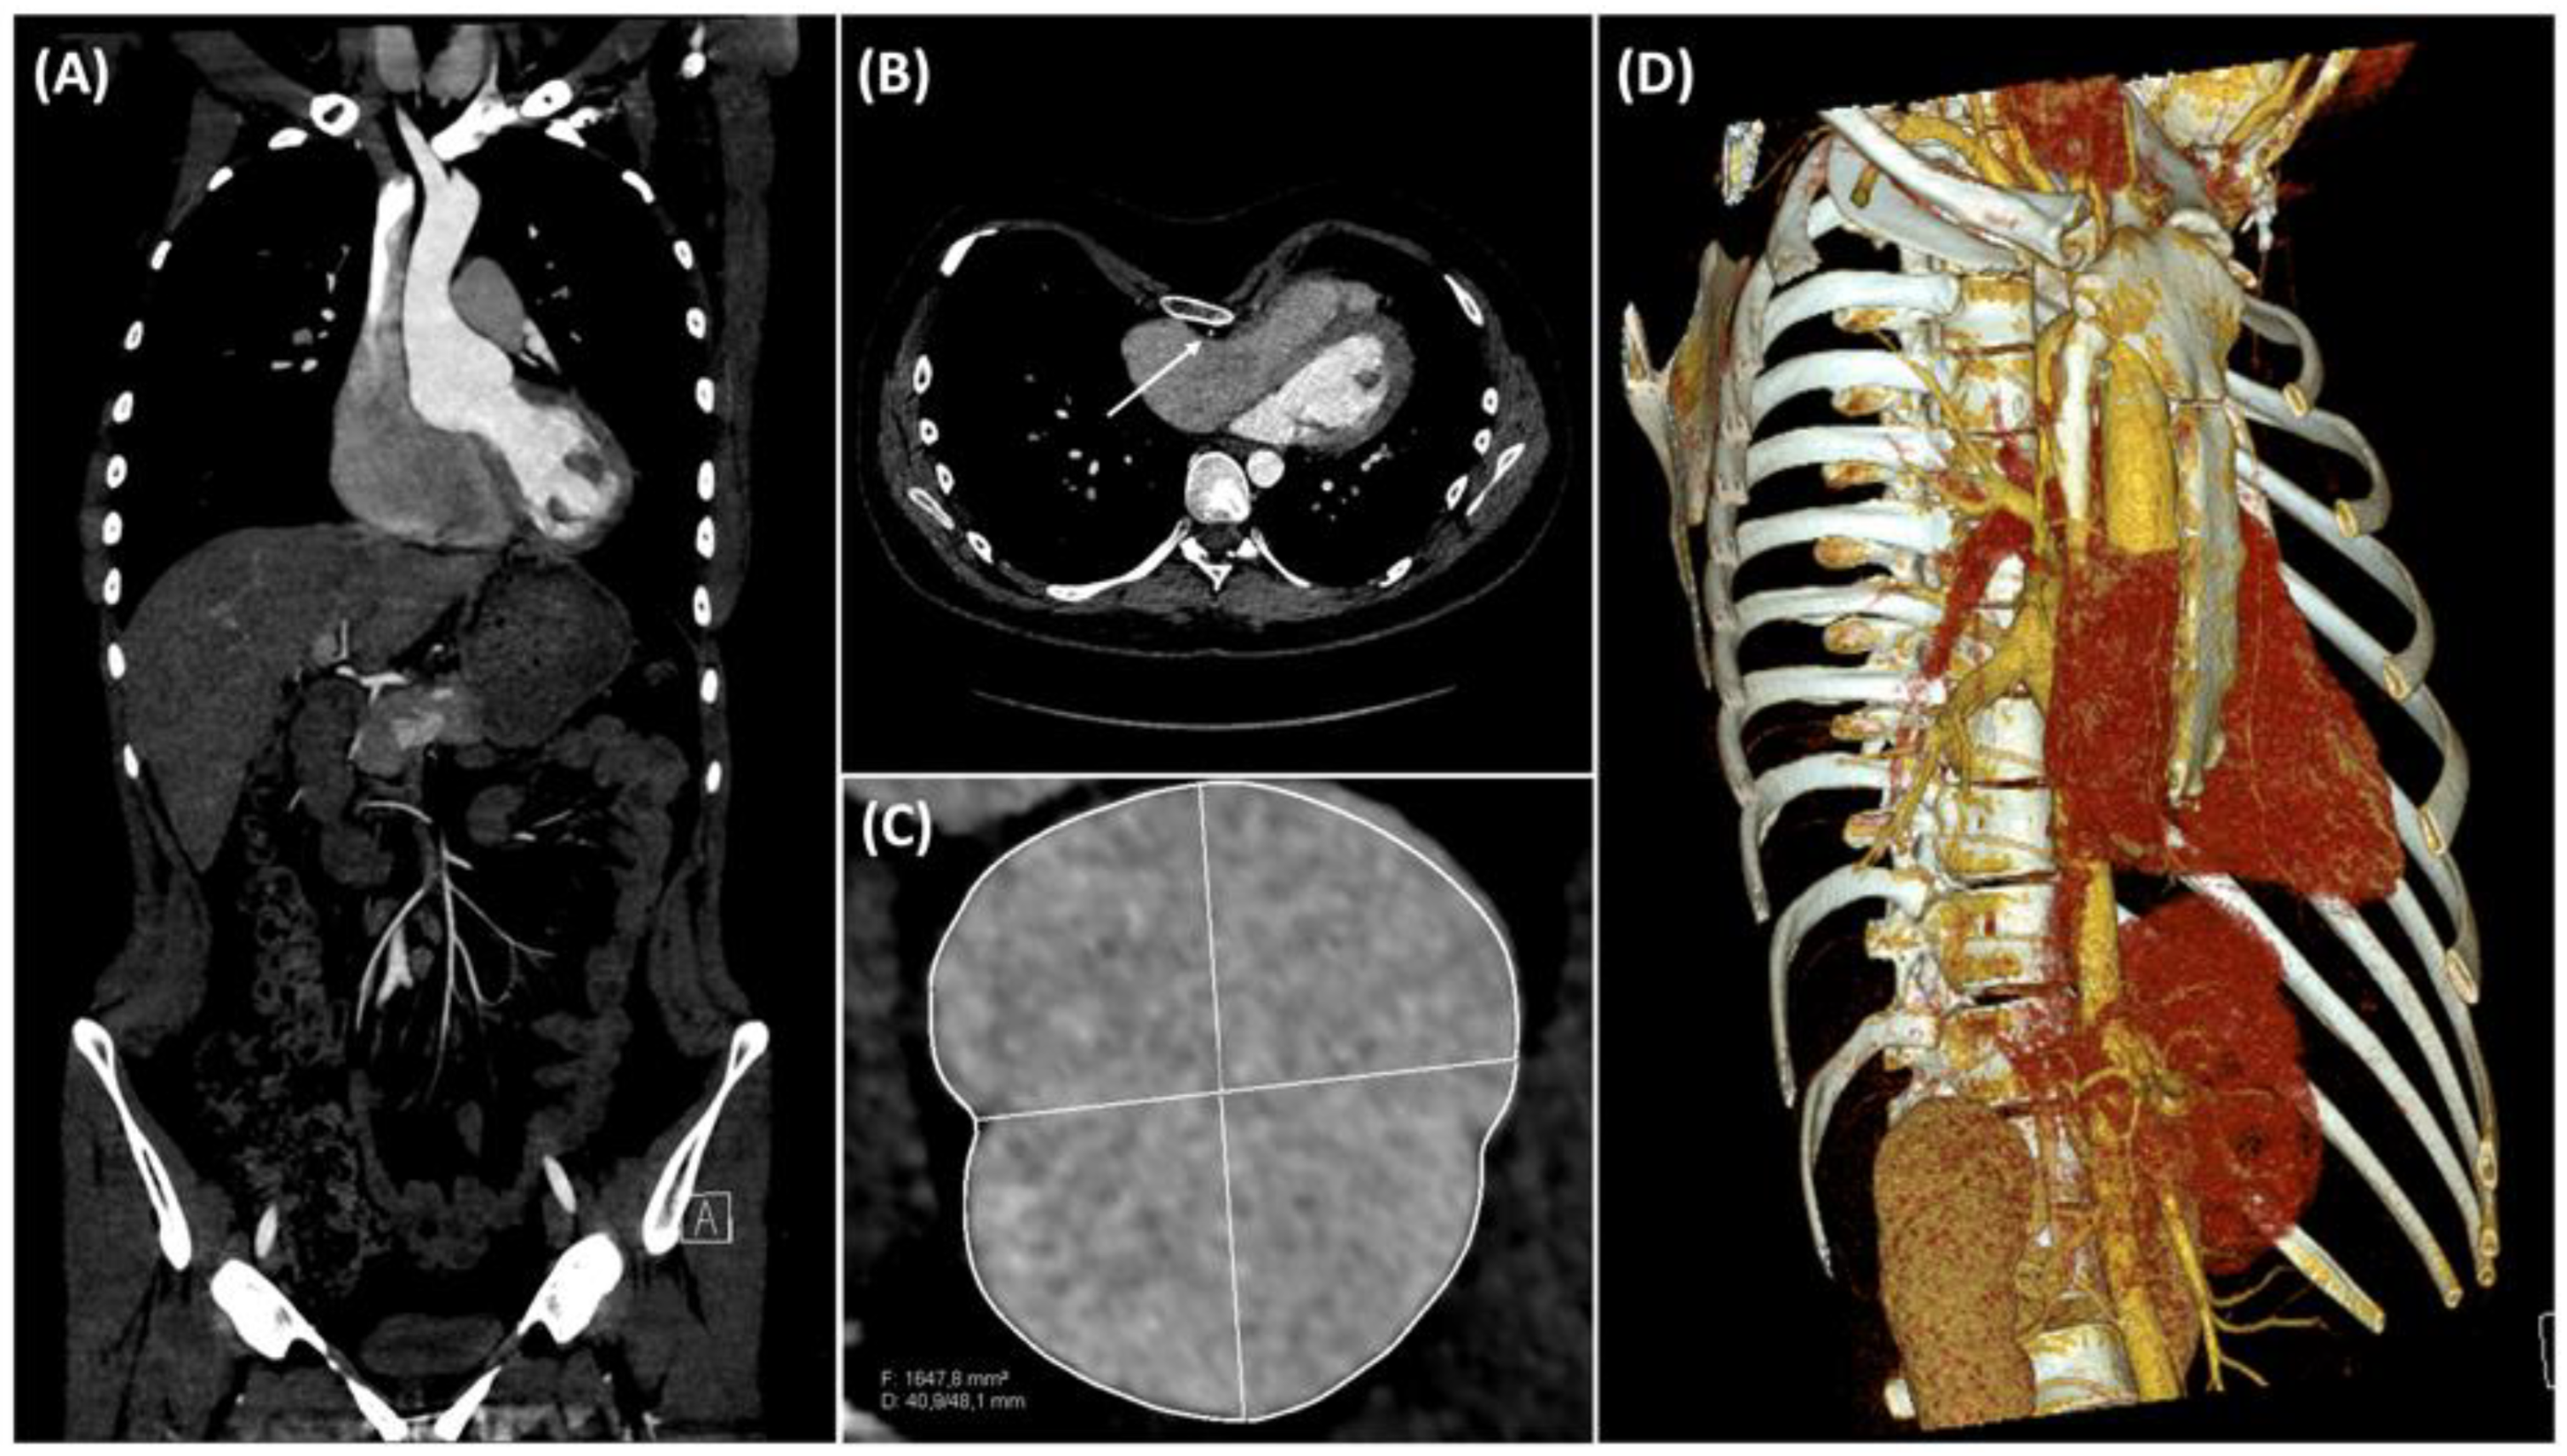

2. Case Description